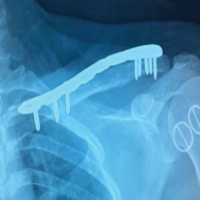

A 64-year-old right-handed woman presented with the sudden onset of severe right wrist pain sustained after a fall. Physical examination demonstrated swelling and tenderness along the ulnar aspect of the volar wrist. Plain radiographs and computed tomography (CT) scans revealed a comminuted intra-articular pisiform fracture featuring a small proximal fragment and articular incongruity with a cortical gap and a step-off (Fig. 1 and 2).

Figure 1: Initial plain radiographs demonstrate an isolated displaced intra-articular pisiform fracture with pisotriquetral joint incongruity.

Figure 3: Intraoperative fluoroscopic image after hook plate fixation illustrates reduction and plate compression across the fracture, with the hook engaging the proximal aspect of the pisiform.